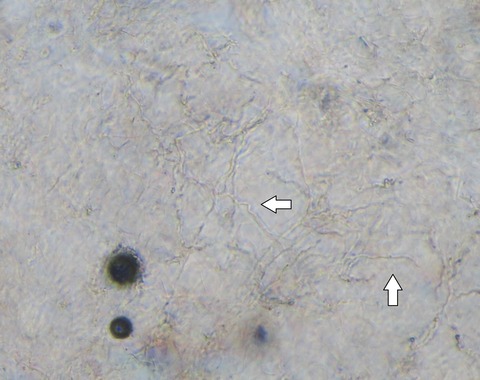

これまでのブログで書きました糸状菌がいますね。

10倍なので黒い四角で囲った部分を20倍で見てみます。

糸状菌が分かりやすいですね。

菌が活動的な周辺が赤くなりますので環状紅斑になります。